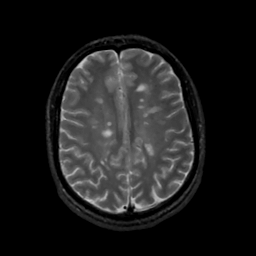

MR Study #1, February 10, 1991 -- Slice #34

[Home][Help][Clinical][Tour 1][Tour 2] Slice 34